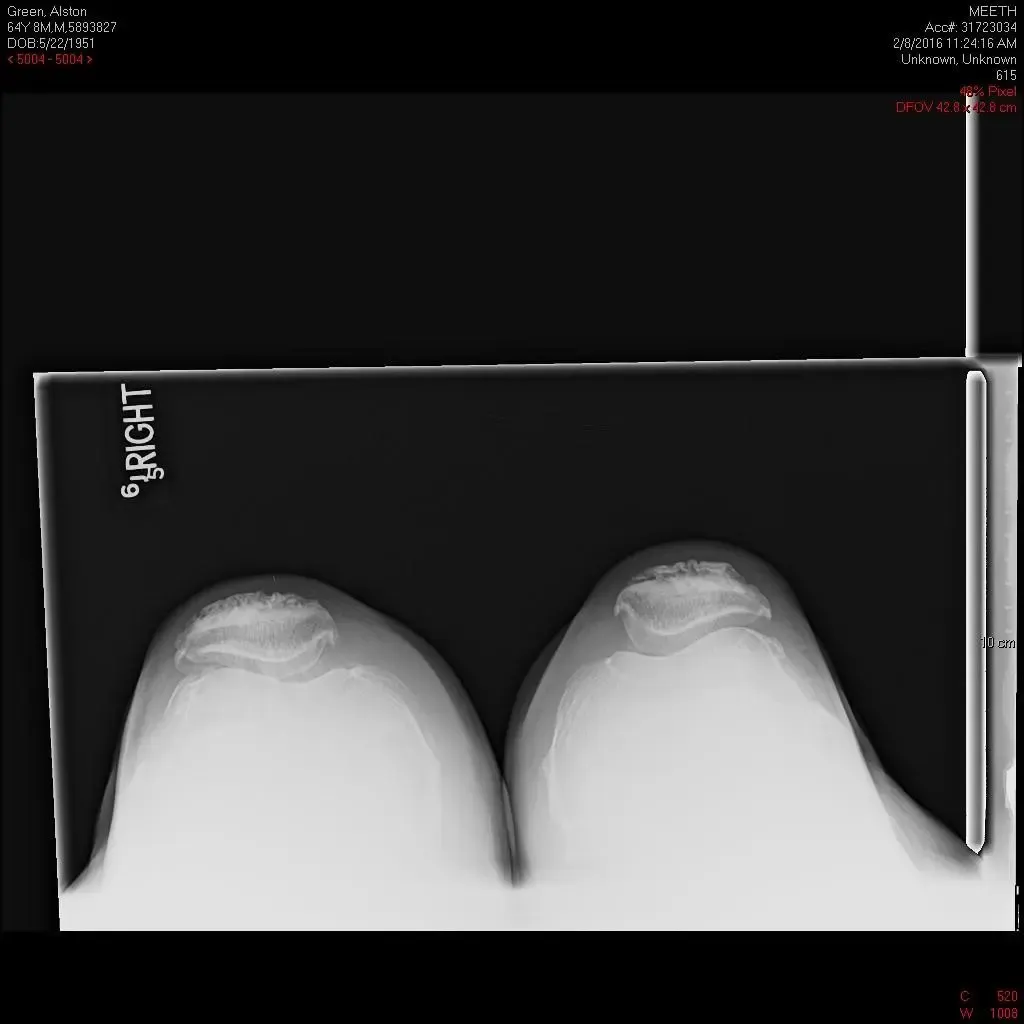

Radiografía preoperatoria de la rodilla derecha en vista lateral y vista del horizonte.